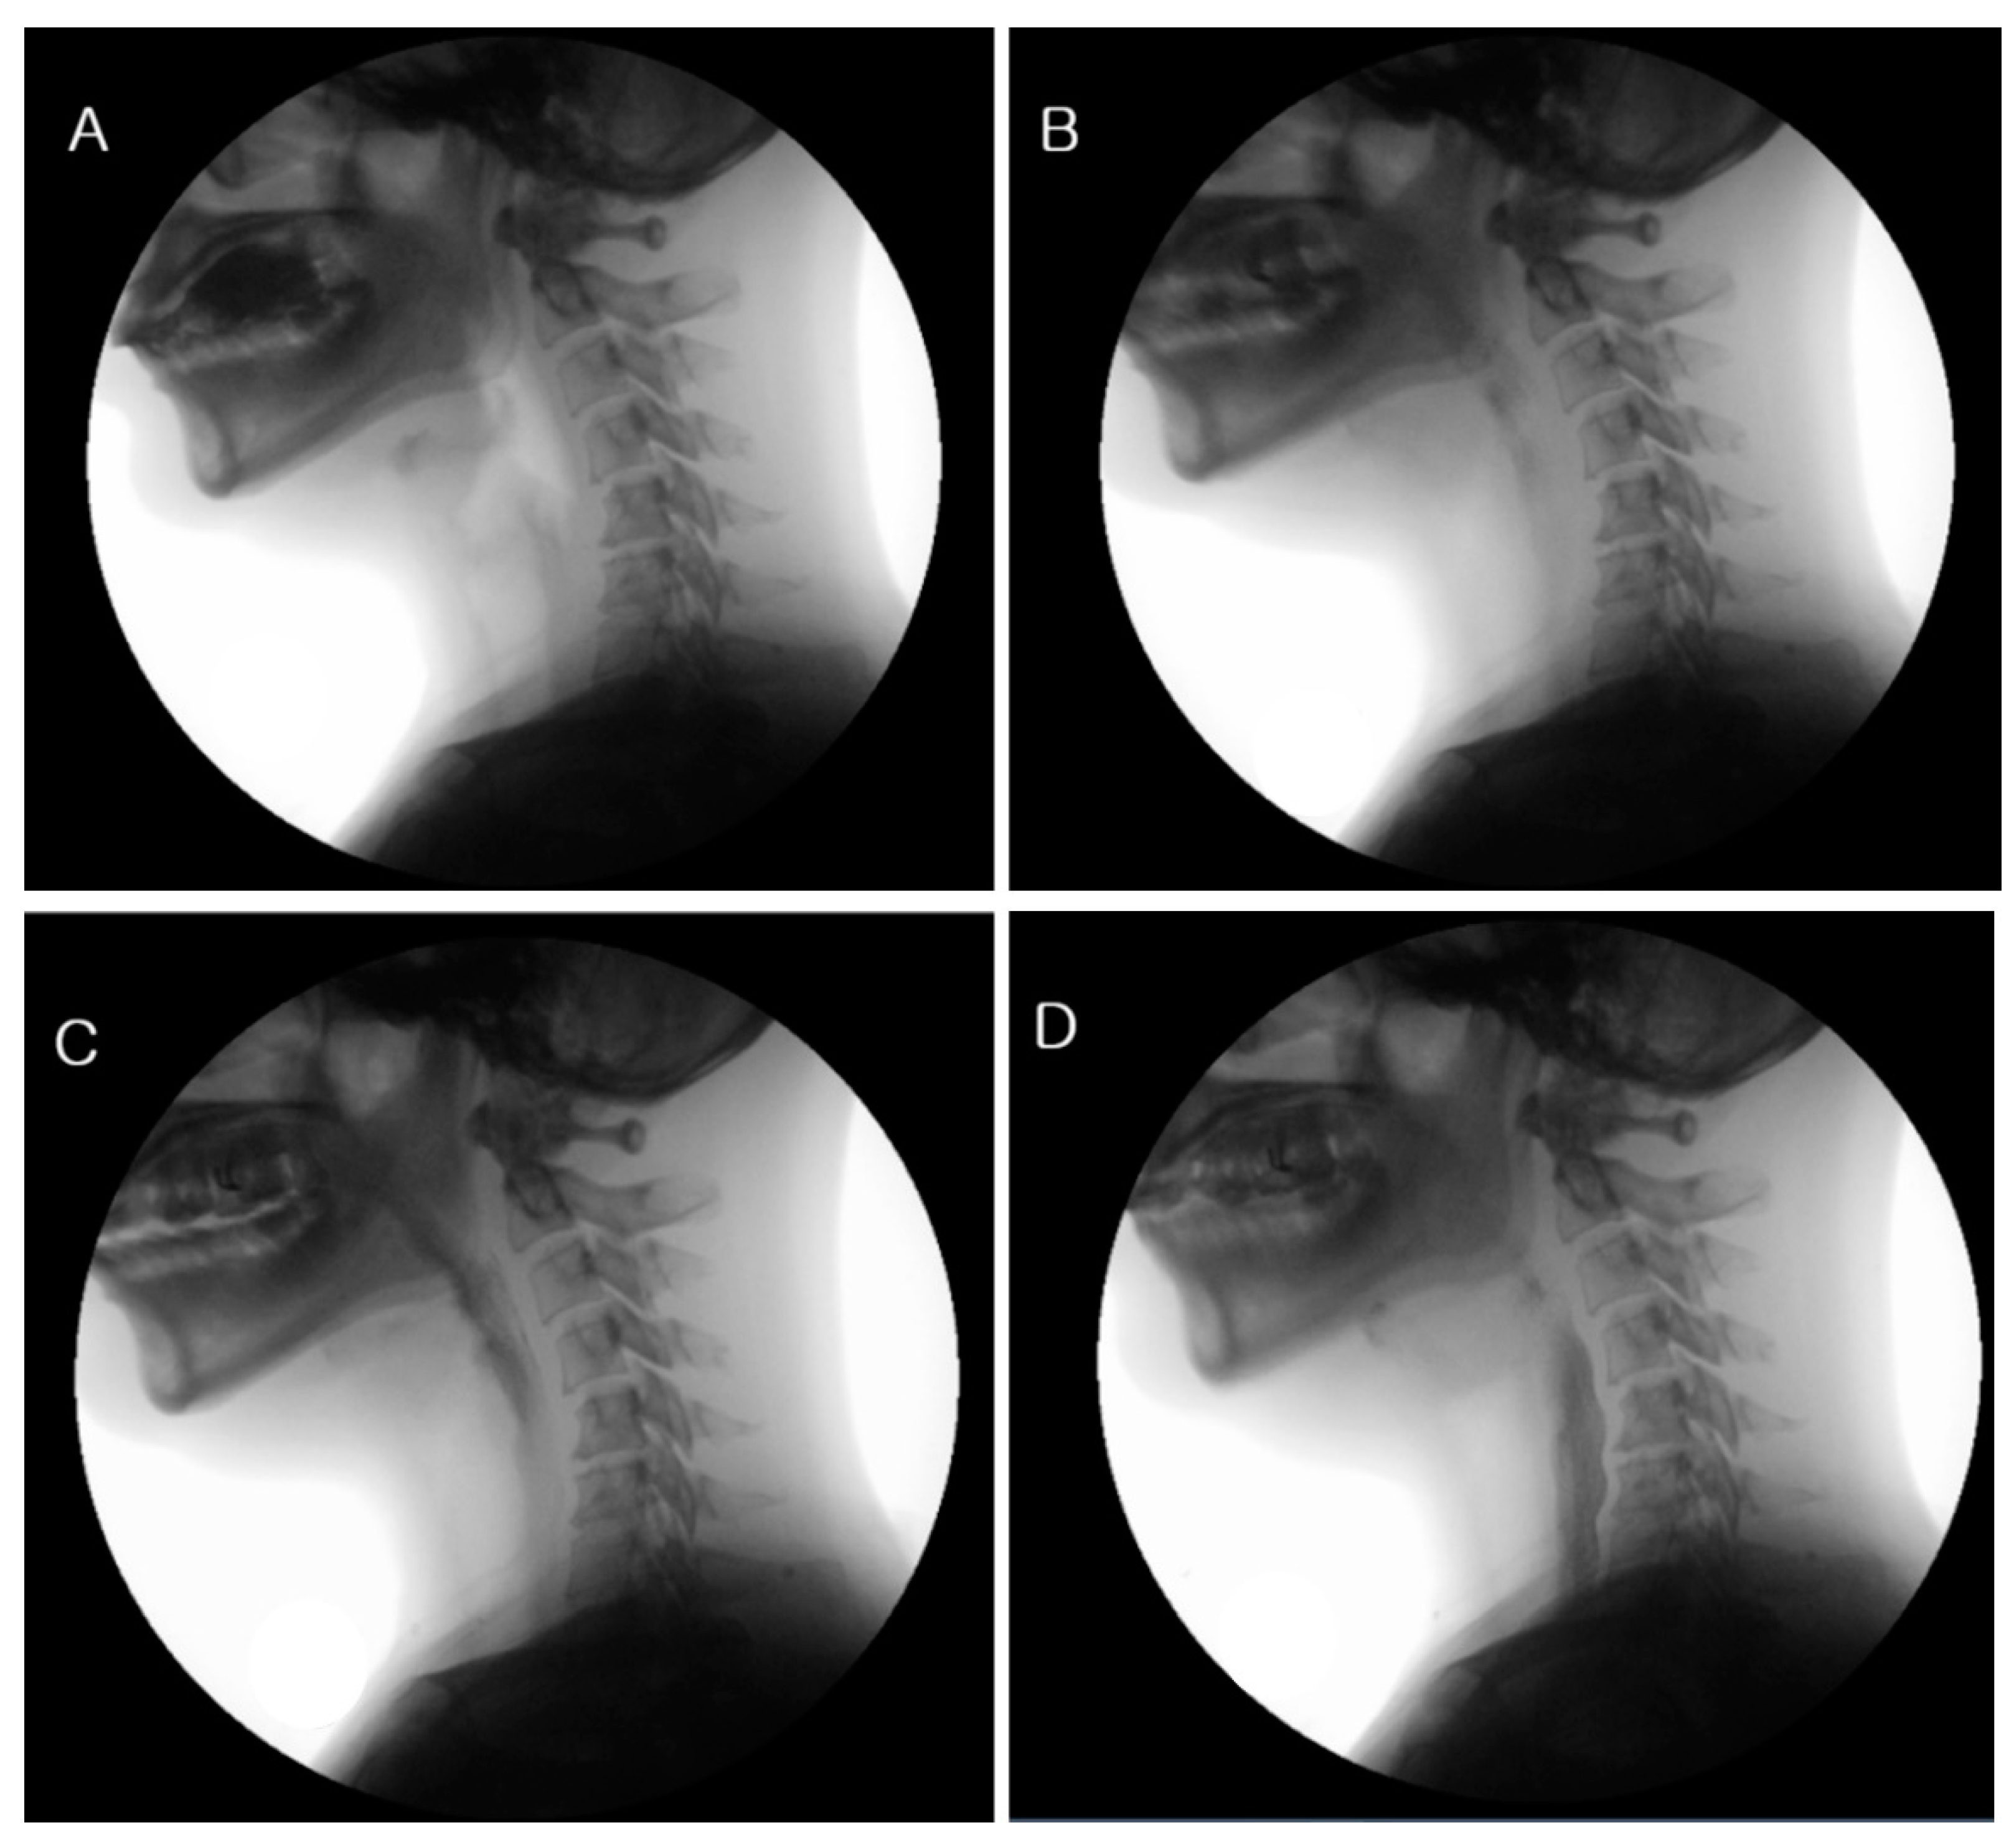

2.2.2. VFSS (Videofluoroscopic Swallowing Study)

3.1. VFSS